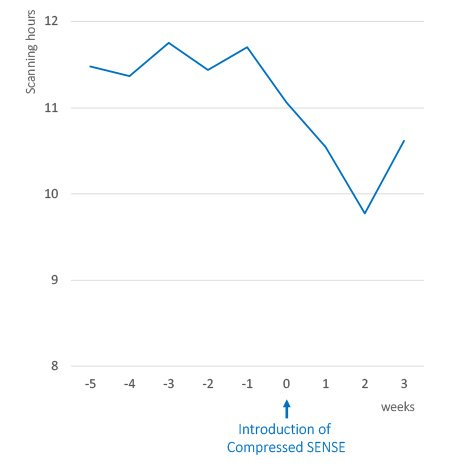

Reduce overtime

Reduction in overtime, while maintaining same patient throughput per day.

We frequently encounter MRI Departments whose MRI scanners are fully booked. This can mean scanning continues past regular opening hours and staff have to work overtime. Compressed SENSE can make MRI examinations shorter and more manageable, helping patients and staff get home on time. Compressed SENSE has reduced their staff overtime through shorter time slots and more flexible scheduling.1

Decreased staff overtime, maintain patient throughput

After implementing Compressed SENSE at CTI Innsbruck, Austria reduced staff overtime by more than one hour, while maintaining the same patient throughput per day.